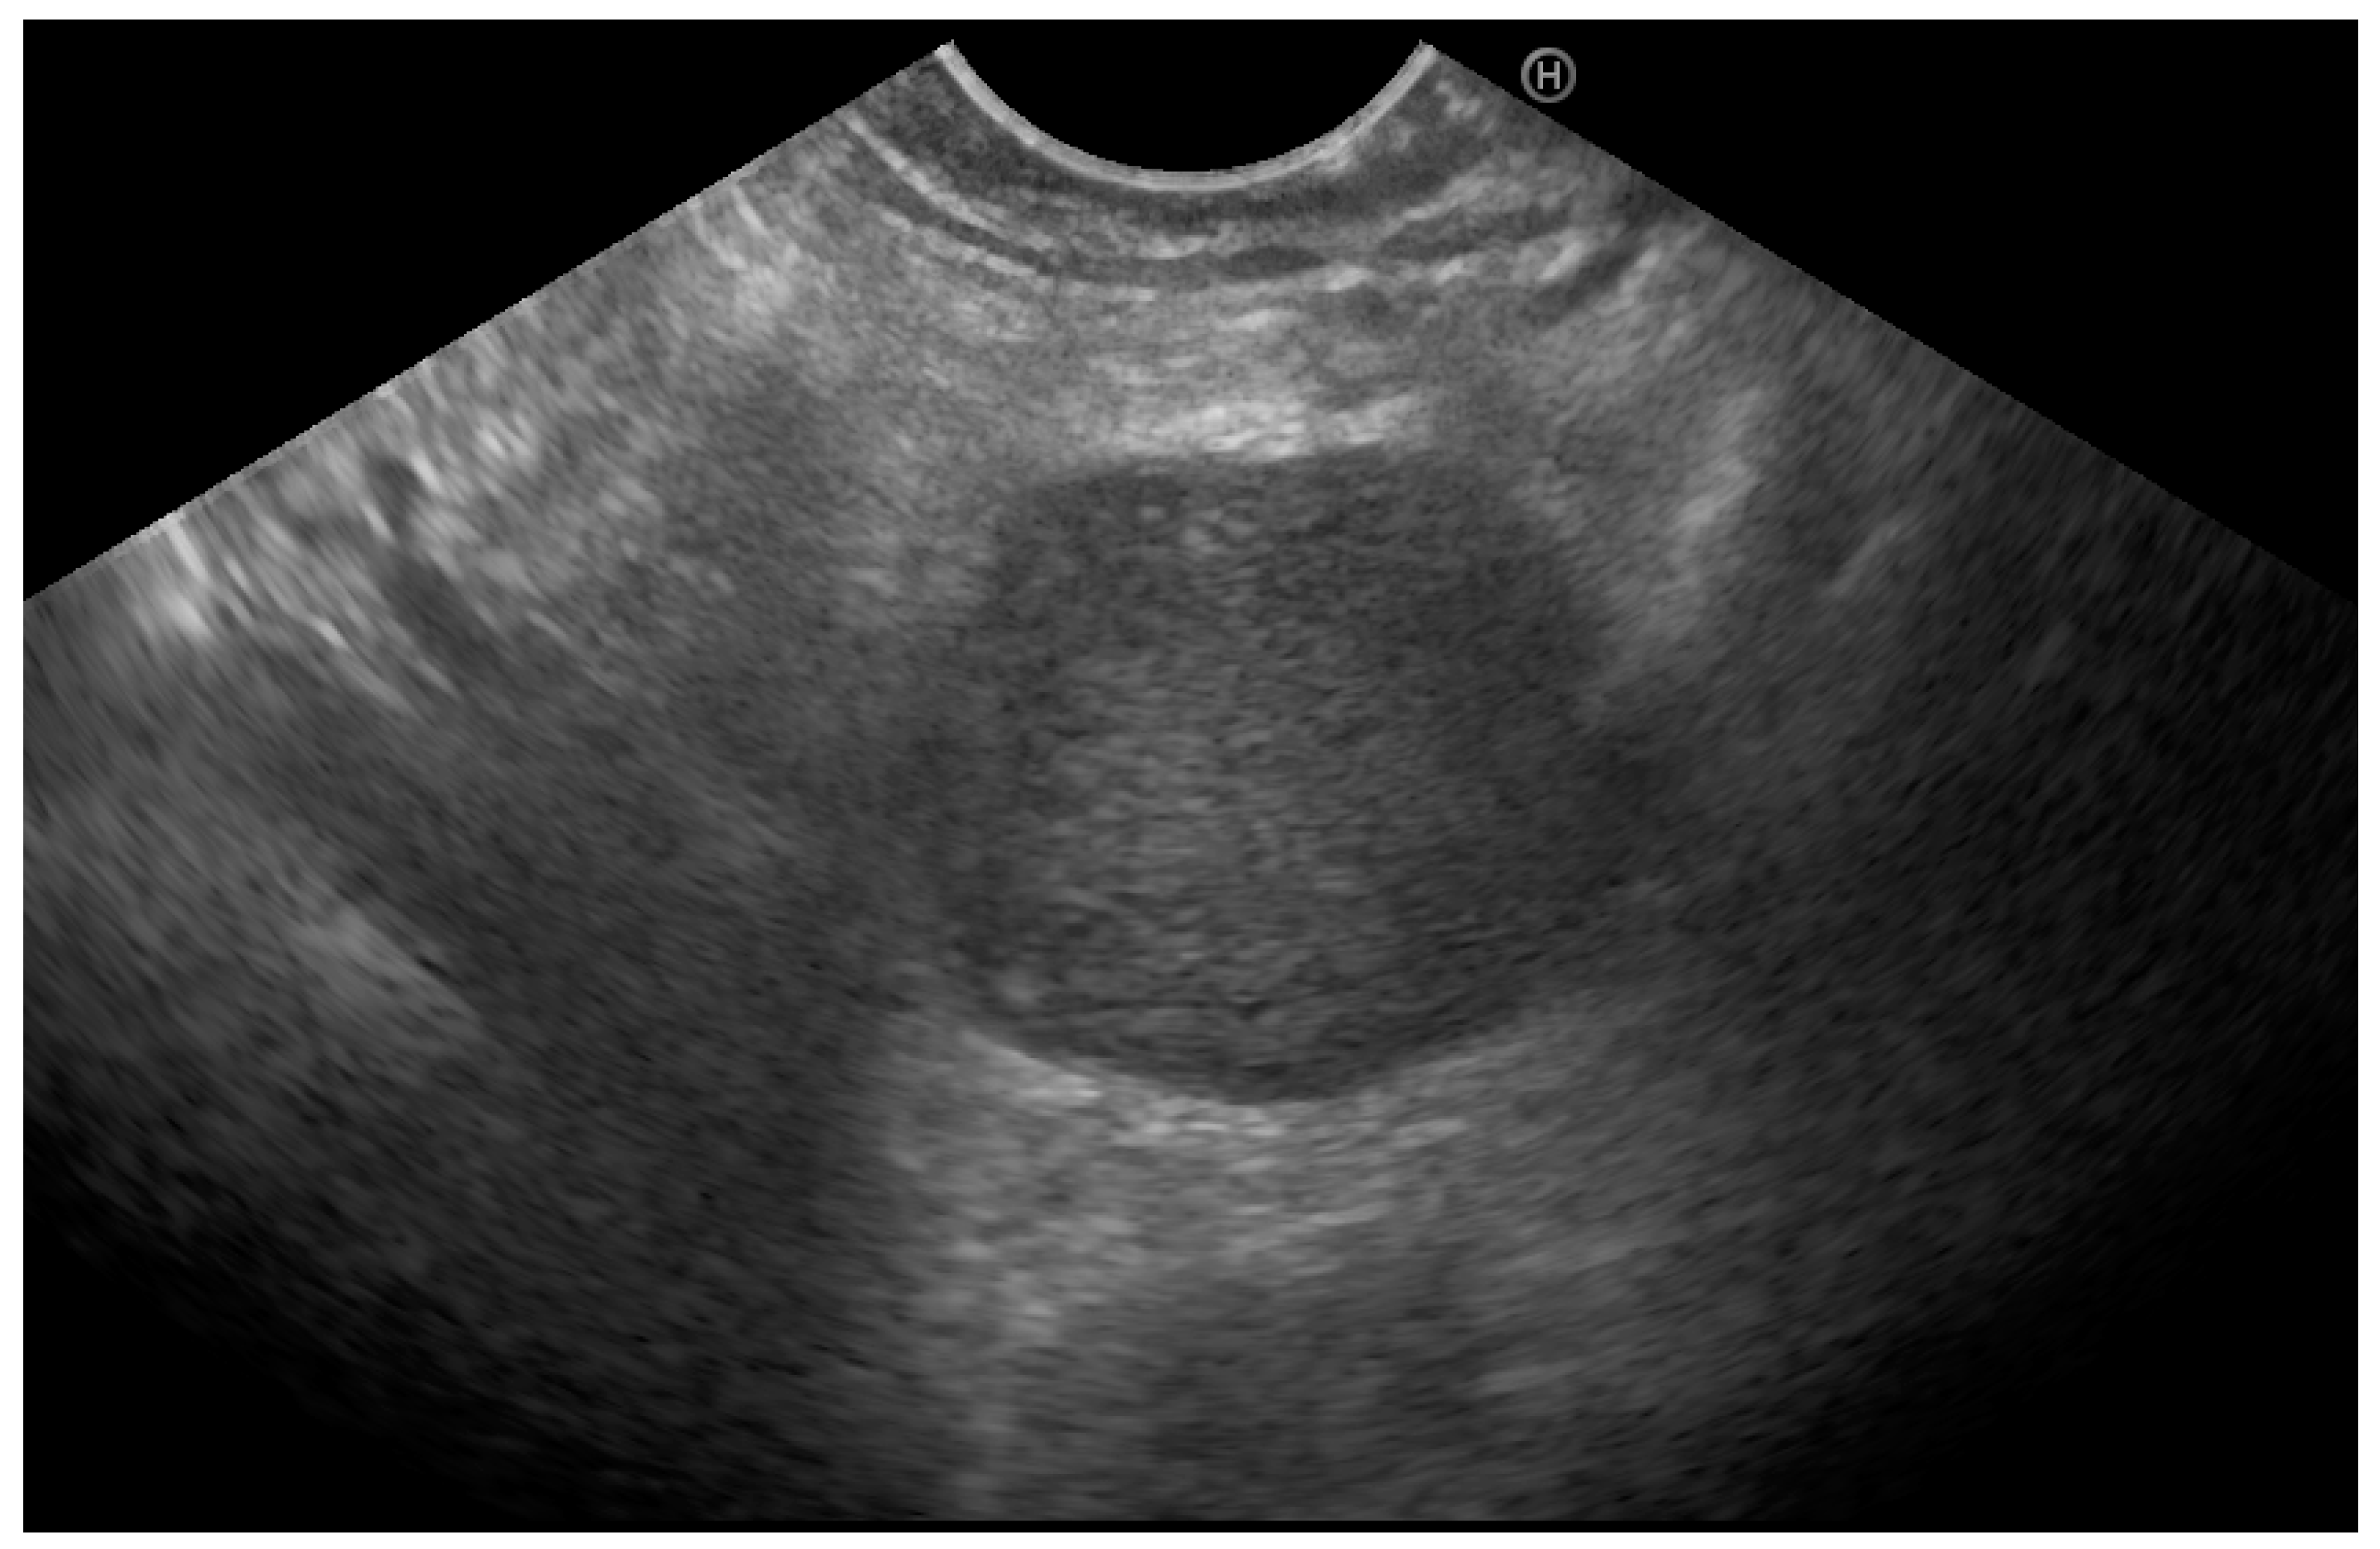

- Seicean, A.; Mosteanu, O.; Seicean, R. Maximizing the endosonography: The role of contrast harmonics, elastography and confocal endomicroscopy. World J. Gastroenterol. 2017, 23, 25–41. [Google Scholar] [CrossRef]

- Iglesias-Garcia, J.; Lindkvist, B.; Lariño-Noia, J.; Abdulkader-Nallib, I.; Dominguez-Muñoz, J.E. Differential diagnosis of solid pancreatic masses: Contrast-enhanced harmonic (CEH-EUS), quantitative-elastography (QE-EUS), or both? United Eur. Gastroenterol. J. 2017, 5, 236–246. [Google Scholar] [CrossRef]

- Ignee, A.; Jenssen, C.; Arcidiacono, P.G.; Hocke, M.; Möller, K.; Saftoiu, A.; Will, U.; Fusaroli, P.; Iglesias-Garcia, J.; Ponnudurai, R.; et al. Endoscopic ultrasound elastography of small solid pancreatic lesions: A multicenter study. Endoscopy 2018, 50, 1071–1079. [Google Scholar] [CrossRef]

- Eloubeidi, M.A.; Jhala, D.; Chhieng, D.C.; Jhala, N.; Eltoum, I.; Wilcox, C.M. Multiple late asymptomatic pancreatic metastases from renal cell carcinoma: Diagnosis by endoscopic ultrasound-guided fine needle aspiration biopsy with immunocytochemical correlation. Dig. Dis. Sci. 2002, 47, 1839–1842. [Google Scholar] [CrossRef]

- Pannala, R.; Hallberg-Wallace, K.M.; Smith, A.L.; Nassar, A.; Zhang, J.; Zarka, M.; Reynolds, J.P.; Chen, L. Endoscopic ultrasound-guided fine needle aspiration cytology of metastatic renal cell carcinoma to the pancreas: A multi-center experience. CytoJournal 2016, 13, 24. [Google Scholar] [CrossRef] [PubMed]